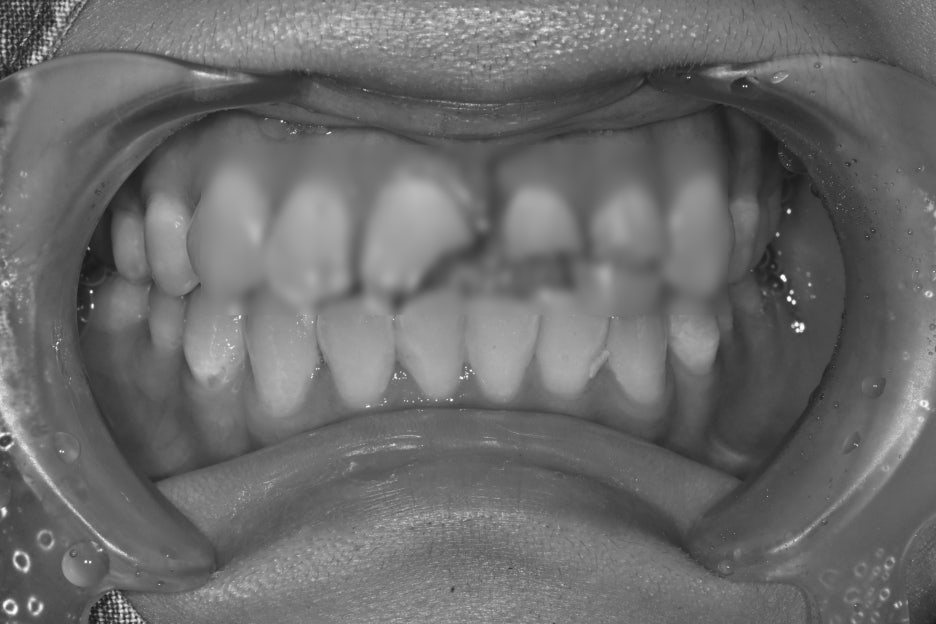

Before and after treatment photos

Photos before and after treatment